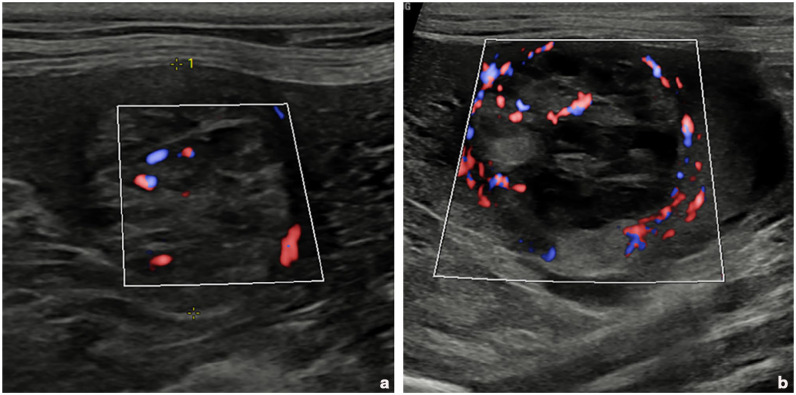

Case summary: An 8-year-old female neutered domestic shorthair cat was referred for further investigations of lethargy, polyuria, polydipsia, hyporexia and weight loss. One month prior, the cat had been diagnosed with normotensive and non-proteinuric chronic kidney disease and a single small well-defined splenic nodule thought to represent a benign process. Specialist abdominal ultrasonography documented changes suggestive of pyelonephritis alongside a solitary splenic mass (2 cm in size). Follow-up imaging 4 weeks later showed progression of the splenic mass (3.5 cm) and a novel marked anaemia. Splenectomy and histopathology were performed, which confirmed a diagnosis of splenic haemangiosarcoma. The cat was started on metronomic thalidomide (5 mg/kg PO q24h; BOVA) 16 days postoperatively. The cat re-presented to the referring veterinary practice 169 days after splenectomy (153 days after starting metronomic thalidomide) owing to lethargy and hyporexia. Abdominal ultrasound identified a solitary hepatic mass and free peritoneal fluid; the cat was subsequently euthanased without further investigations.

Relevance and novel information: This is the first published case report documenting the management of splenic haemangiosarcoma in a cat with splenectomy and metronomic thalidomide. Our observations indicate that survival time falls in line with other chemotherapeutic protocols and that thalidomide side effects were limited to mild polyphagia and moderate sedation, which was tolerated well if the drug was administered in the evening.